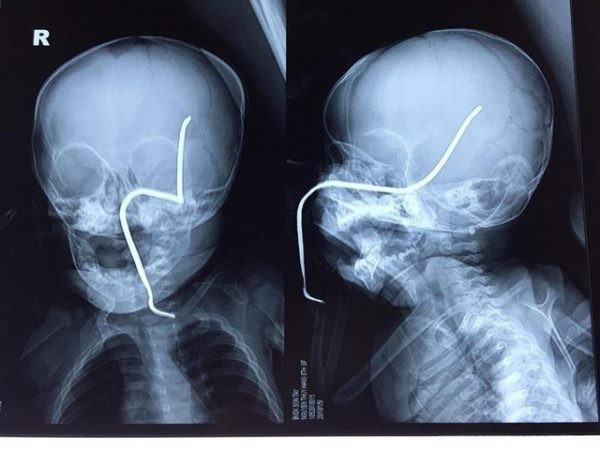

Hình ảnh thanh sắt đâm xuyên vào hộp sọ bệnh nhi. Ảnh: BVCC

Ths.Bs Hồ Trung Luân, khoa Ngoại Thần kinh, người trực tiếp phẫu thuật cho bệnh nhi cho biết: Ca mổ này khá khó khăn do thanh sắt đâm vào gò má trái qua tổ chức phần mềm của má, đâm thủng sàn sọ, xuyên qua vùng não thái dương và vùng đỉnh sát các mạch máu lớn. Thanh sắt đã cũ, giòn nên rất dễ gãy, lại nằm sát các mạch máu nên nguy cơ chảy máu trong mổ là rất lớn, đồng thời bệnh nhi cũng phải đối mặt với nguy cơ nhiễm trùng não, áp-xe não cũng rất cao.

Cũng theo bác sĩ Luân, ca mổ kéo dài hơn 30 phút, các bác sĩ đã gắp dị vật ra an toàn. Hiện trẻ đang được tiếp tục theo dõi sau mổ, kiểm soát tình trạng phù não, chống nhiễm trùng, chảy máu tại khoa Hồi sức ngoại.